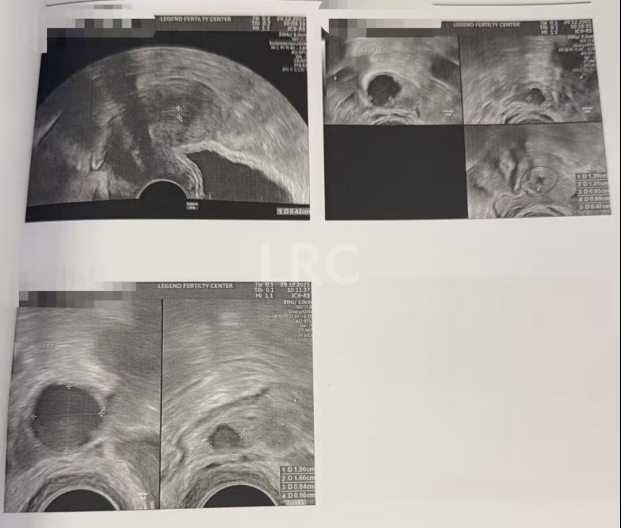

促排第三天

阴超检查(只数能用卵子):

- 右侧卵泡 2 颗 (9,4mm)

- 左侧卵泡 2 颗 (11,5mm)

激素水平检查:

- 促黄体生成素 6.00 miu/ml

促排第六天

阴超检查:

- 右侧卵泡 2 颗 (13,9mm)

- 左侧卵泡 2 颗 (17,7mm)

- 促黄体生成素 12.00 miu/ml

子宫内膜厚度:4.0 mm

促排第十天

- 右侧卵泡 2 颗 (20,15mm)

- 左侧卵泡 2 颗 (23,7mm)